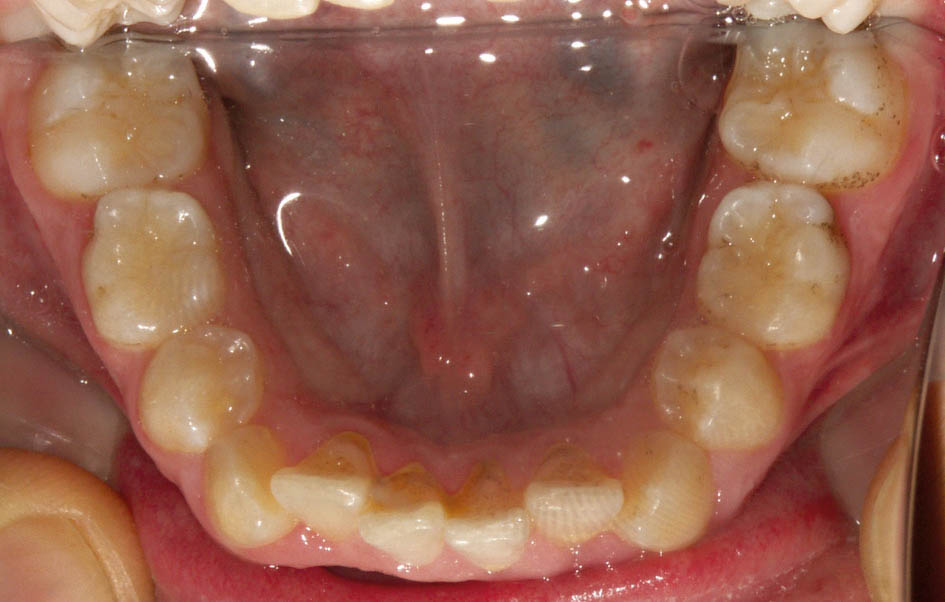

عرض 3 و 4 بزرگتر از دندانهای شیری مربوطه است، لذا با رویش آنها کرادینگ کمی در این ناحیه رخ میدهد (شکل 8-5). در زمان رویش پرمولر دوم (حدود سن 11 سالگی) فقط دندان E در دهان باقی مانده است. چون عرض مزیودیستالی آن 2.5mm بیشتر از عرض دندان 5 است، پس در حدود 12-11 سالگی که دندان E میخواهد لق شود میتوانید یک نگهدارنده فضا مانند لینگوال آرچ (شکل 9-5) بسازید (قبل از افتادن یا کشیدن E) و بعد دندان E را بکشید. یک سال بعد که دندانهای 5 رویش یافتند، در هر سمتی 2.5mm فضا خواهید داشت و میتوانید آن مقدار کرادینگ را برطرف کنید.

شکل 8-5: با رویش دندانهای 3و4 کرادینگ بیمار بیشتر میشود.